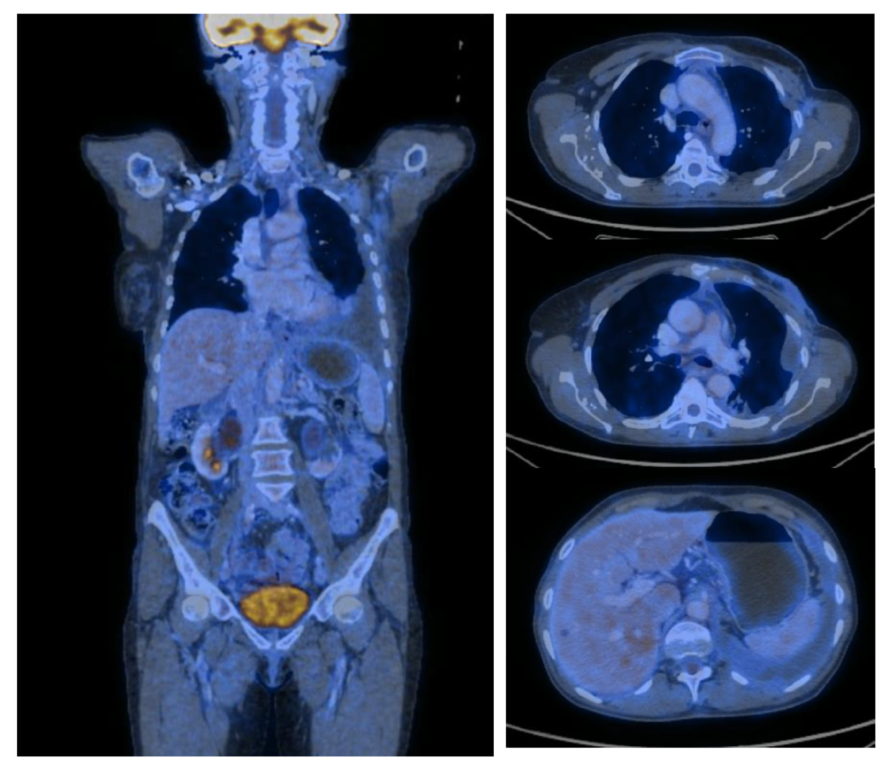

2. Case Report

| PET-CT | Positron Emission Tomography |

| SUV | Standardized Uptake Values |